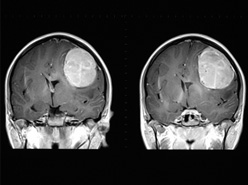

• Imaging: CT or MRI of the brain

• Some causes, such as a brain tumor, could be treated

• If we are considering epilepsy surgery, knowing the location of a lesion could help with the surgical planning